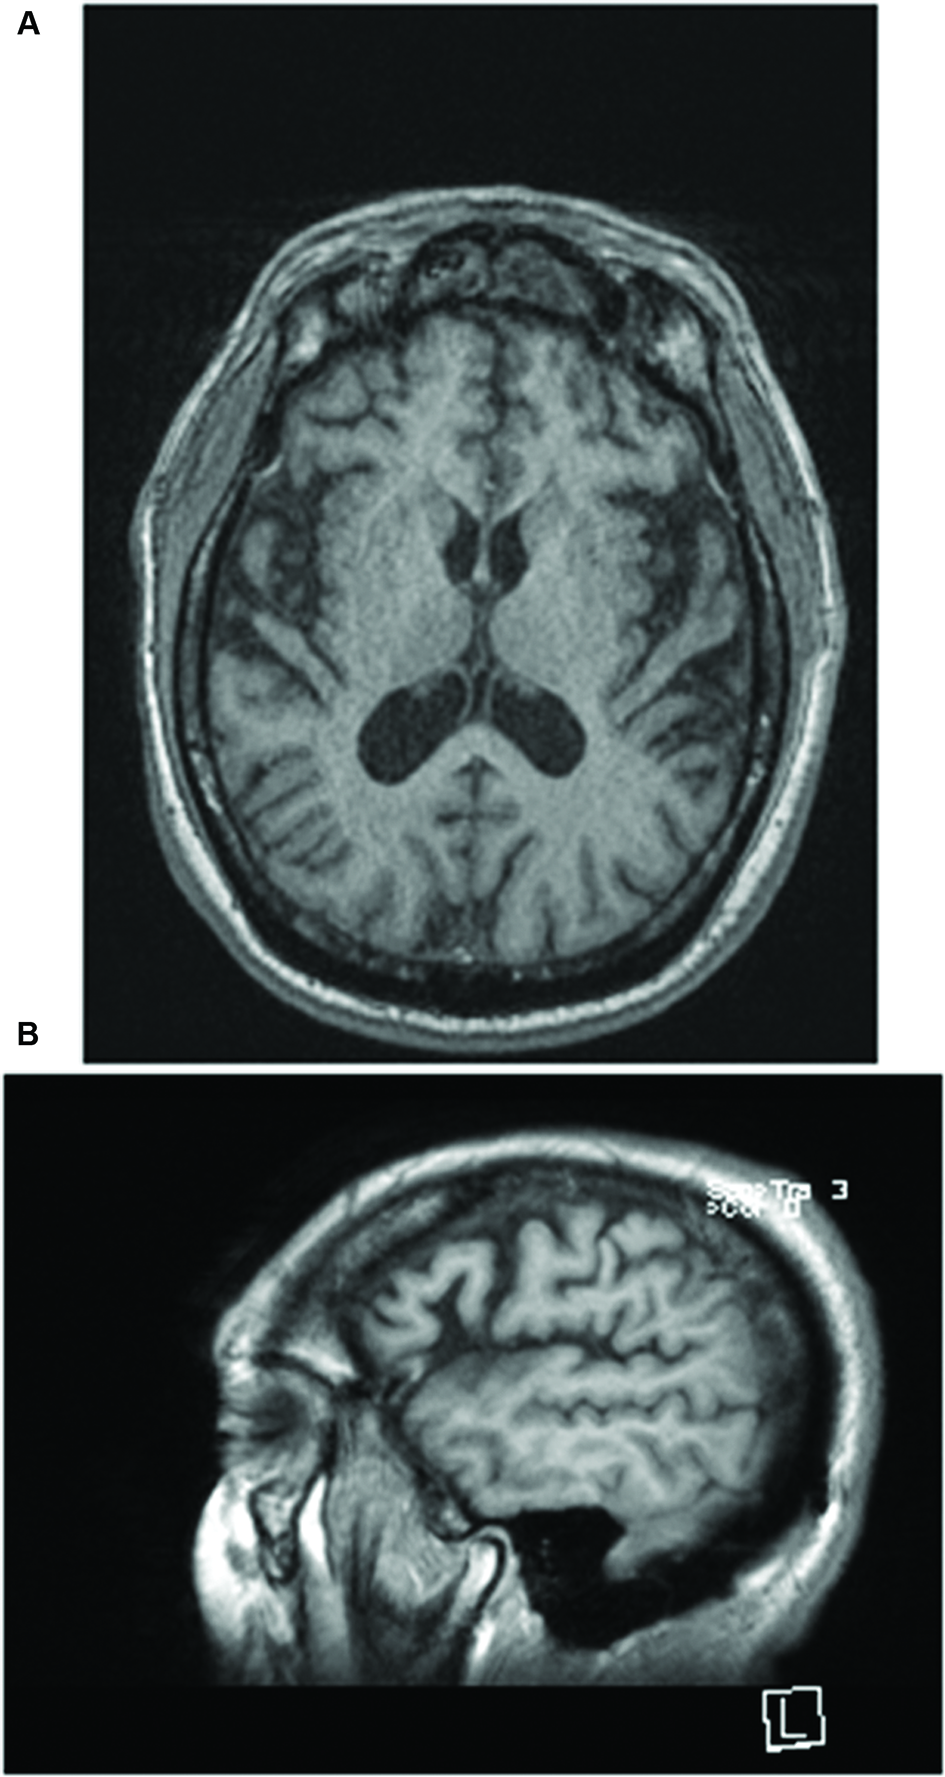

Magnetic resonance imaging (MRI) performed in April 2015 revealed mild global volume loss for age with widening of the Sylvian fissure bilaterally. Neither evidence of past acute TBI or white matter abnormalities were noted on fluid-attenuated inversion recovery (FLAIR) imaging (Figure 1). Neuropsychological testing administered during the index hospitalization was significant for impairment on tasks of processing speed, simple attention, verbal learning and memory, aspects of executive functioning (set-shifting, verbal fluency), facial recognition, and affect naming and recognition. Aspects of visuospatial discrimination and construction, confrontation naming, and visual memory were intact (Table 1).

FIGURE 1. (A) T1 axial and (B) sagittal images of the brain obtained 9 months earlier demonstrate mild global volume loss for age with widening of the Sylvian fissure bilaterally. Neither evidence of past acute TBI nor white matter abnormalities were noted on fluid-attenuated inversion recovery (FLAIR) imaging.